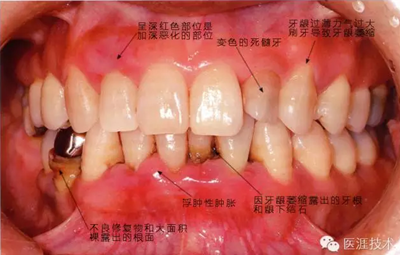

44歲牙周炎女性的臨床照片

a18.png

44歲患有糖尿病病史(未治愈)。菌斑控制不良。通過牙周探診,全頜有4~8mm的牙周袋,在X光片中可以看到上頜前牙處中度牙槽骨吸收,磨牙處重度牙槽骨吸收。二次齲齒和根面齲齒也有發(fā)生。可以看到浮腫性腫脹,收到刺激后會出血。